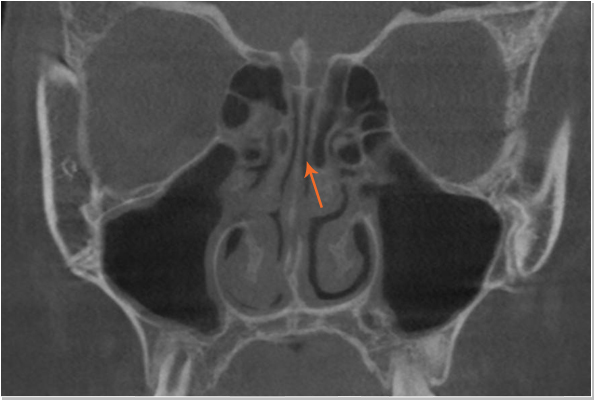

낮은코 내부구조 CT 사진 비중격 만곡증

낮은코 내부구조 CT 사진 커져있는 코덧살(비염)